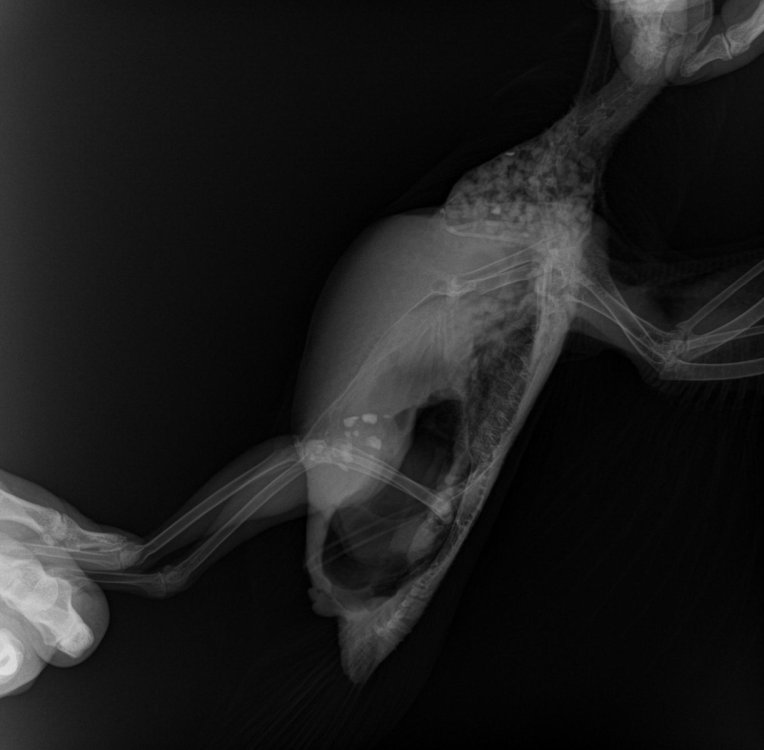

Уголь активированный с водой 2 мл, через два часа вазелиновое масло 2 мл. Он ожил, глистов больше не видел. Не пойму, у него то ли было повреждено крыло, свисает, то ли он в переноске повредил. Пока зафиксировал одно за туловище на конце. Вы можете посоветовать, к кому можно обратиться в Москве или Подмосковье, чтобы посмотрели и сделали перевязку? В Химках не берут с улицы лечить. Сегодня дал 0.3 мл суспензию детскую Ибупрофена 0.3 мл и намазал немного Троксевазином. Хочу его немного беспокоить, очень прыткий.